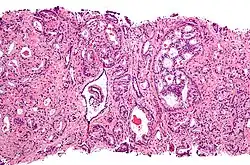

-

Gleason score 6 (3+3) -

Cribriform pattern: Gleason grade 4 -

Gleason score 7 (3+4) with minor component of cribriform glands -

Gleason score 8 (4+4) with glomeruloid glands -

Gleason score 8 (4+4) with irregular cribriform glands -

Gleason score 8 (4+4) with fused glands with cytoplasmic vacuoles -

Gleason score 8 (4+4) with poorly-formed glands -

Gleason score 9 (4+5) with cribriform glands, some with necrosis -

Gleason score 10 (5+5) with cords of cells -

Gleason score 10 (5+5) with individual cells -

Gleason score 10 (5+5) with solid sheets of cells

Gleason 3

Gleason 3 is a clearly infiltrative neoplasm, with extension into adjacent healthy prostate tissue. The glands alternate in size and shape, and are often long/angular. They are usually small/micro-glandular in comparison to Gleason 1 or 2 grades. However, some may be medium to large in size. The small glands of Gleason 3, in comparison to the small and poorly defined glands of pattern 4, are distinct glandular units. Mentally you could draw a circle around each of the glandular units in Gleason 3.[4][7]

Gleason 4

Gleason pattern 4 glands are no longer single/separated glands like those seen in patterns 1–3. They look fused together, difficult to distinguish, with rare lumen formation vs Gleason 1–3 which usually all have open lumens (spaces) within the glands, or can be cribriform-(resembling the cribriform plate/similar to a sieve: an item with many perforations). Fused glands are chains, nests, or groups of glands that are no longer entirely separated by stroma-(connective tissue that normally separates individual glands in this case). Fused glands contain occasional stroma giving the appearance of "partial" separation of the glands. Due to this partial separation, fused glands sometimes have a scalloped (think looking at a slice of bread with bite taken out of it) appearance at their edges.[4][7]